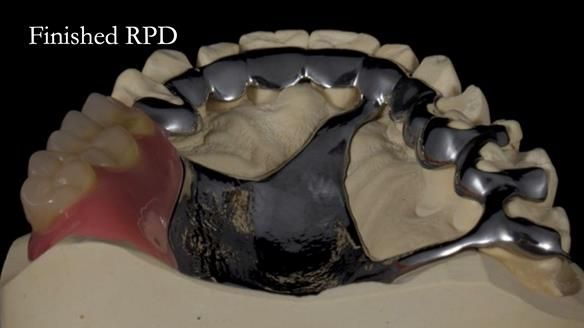

Welcome to Newsletter 64. I'll walk you through the process of providing a Mk 2 metal-based partial denture (RPD), for Ian a retired Veterinary Surgeon aged 78. The RPD was made at an increased vertical dimension and acted as an occlusal stabilisation splint - reducing the wear and bite force on the remaining natural teeth.